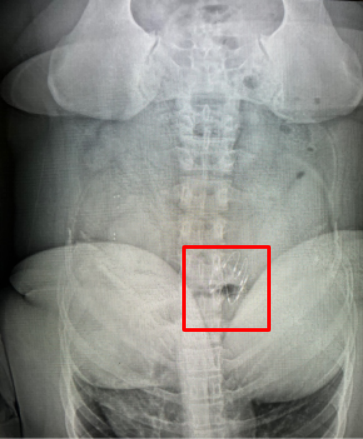

支架置入后第二天复查DR

三个月后的8月20日,到了取出支架的时刻。当复查结果出来时,所有人都为之振奋:小李体重降至149斤,成功减重25斤,减重率达14.4%。更重要的是,她的代谢指标发生了明显改善——甘油三酯下降62%,胆固醇降幅20.2%,恢复至正常范围,糖化血红蛋白也有所降低。支架取出后的一周内,她的体重仍在持续下降,又减轻了2斤。